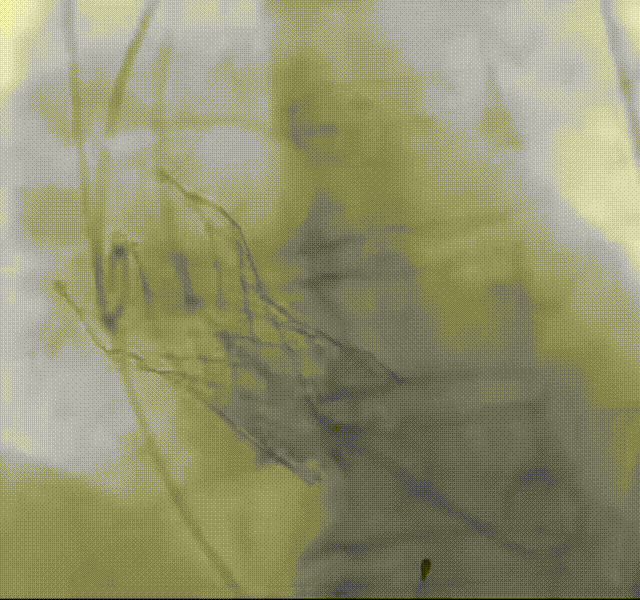

罗建方教授 广东省人民医院(点击查看专家详细简历) 设计本为临床需,耐久守护好芳华:任何医疗产品的设计初衷与最终归宿,都应落在 “临床获益” 这一核心上。尤其在 TAVR 领域,年轻患者预期寿命长,术后瓣膜的长期性能直接关乎其生活质量与生存预后。瓣膜耐久性问题,是落到临床实践中亟待突破的关键课题。传统瓣膜在长期使用中,可能因结构老化、功能退化等问题,难以满足年轻群体数十年的健康需求,二次手术风险也随之攀升。因此,产品设计必须直面这一临床痛点:通过材料革新增强抗钙化性能及生物相容性,以技术突破延长瓣膜有效使用寿命。此次临床应用的预装干瓣Prostyle A®是TAVR领域的革新理念,干瓣预期会为临床提供更耐久性的保障,实现了与临床需求的精准对接,为年轻群体的瓣膜治疗提供更坚实的保障。 李捷教授 广东省人民医院(点击查看专家详细简历) 干瓣技术求革新,性能兼顾护临床:干瓣的技术革新在创新的同时需要和临床实际需求深度耦合,兼顾TAVR术中的核心考量点。临床操作中,瓣膜能否顺利过弓,直接影响手术效率与安全性。Prostyle A®短瓣架设计及第二台阶的柔顺设计,术中操作丝滑;同时,瓣膜植入后的径向支撑力必须平衡得当,才能实现稳定锚定;释放后造影显示:瓣膜形态舒展,轻度瓣周漏,舒张压升高,冠脉开口未受影响;瓣周漏是影响术后效果的关键隐患,双层裙边设计通过多重密封机制降低反流风险,为患者长期获益筑牢防线。这些性能的协同优化,最终目的是让干瓣在临床中真正做到 “好用、耐用、安全用”,为患者预后提升提供坚实支撑。 患者病史 患者因 “活动后气促伴头晕 2 月” 入院。 现病史:2月前无诱因出现活动后气促,休息后缓解,伴头晕,夜间阵发性呼吸困难。超声检查发现:主动脉瓣重度狭窄并重度返流(跨瓣流速 4.3m/s,峰值压差 73mmHg);主动脉 + 冠状动脉 CTA 提示主动脉瓣显著钙化,升主动脉及分支粥样硬化,冠状动脉轻度狭窄(RCA 狭窄 30-40%)。 既往史:高血压病史 15 年,规律服药,血压控制稳定。 术前诊断:非风湿性主动脉瓣狭窄伴关闭不全(重度)、心功能 II 级(NYHA)、高血压病 2 级(高危)、冠状动脉粥样硬化。 术前CT 三叶瓣,瓣叶增厚中度钙化,右无交界钙化粘连,瓣环径25.1mm,LVOT 25.1mm,直筒型结构;窦部空间足够,升主未见增宽,瓣环水平夹角55°;冠脉开口位置佳,无冠脉风险;入路散在钙化、外周双侧入路无明显迂曲,双侧内径可、中分叉,左右侧均能够支持20F 大鞘通过。 造影角度及入路 手术策略 右侧股动脉为主入路,左侧为辅助入路;使用20球囊预扩,准备AV26瓣膜,冲洗口朝向3点钟方向送入输送系统性能,初始定位真实瓣环0位释放,最终锚定约瓣下3mm,工作位评估瓣膜稳定性与冠脉情况。 手术过程 根部造影 20mm 球囊预扩无明显腰征 术中使用26号瓣膜,瓣膜释放贴边迅速 80% 工作位观察瓣膜位置良好 释放后造影显示:瓣膜形态舒展,轻度瓣周漏,舒张压由术前30mmHg升为 60mmHg,冠脉开口未受影响。 术后超声:跨瓣流速降至1.6m/s,平均压差降至5 mmHg,心功能显著改善。 Prostyle A®预装干瓣——助力临床最优化解决方案: 1. 抗钙化与耐久性:Micro-EX™专利技术提升瓣膜抗钙化能力,适配患者瓣叶中度钙化的解剖特点,为长期疗效提供保障。 2. 柔顺过弓与精准定位:短瓣架设计 + 远端超滑涂层,确保患者输送系统过弓顺畅;瓣架流入端微直筒设计,让定位贴边更迅速,减少了手术时间; 3. 80% 可回收设计:便于术中调整观察,减少起搏时间,从而减少并发症。 4. 简化手术流程:预装设计缩短操作时间,20F 大鞘兼容外周入路,降低血管损伤风险。 · END ·